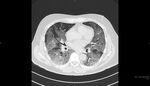

第3波到来するも重症化しにくくなったのはなぜ?

実録・新型コロナウイルス集中治療の現場から(第27回)